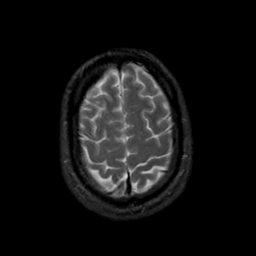

MR Study #19, August 25, 1991 -- Slice #42